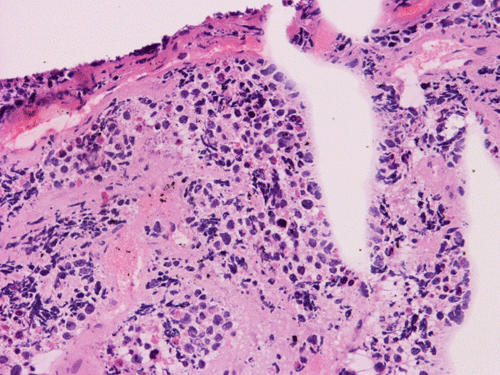

On permanent sections, there is extensive necrosis (Panel G) and there are numerous small islands of pyknotic or apototic nuclei (Panel H). In non-necrotic areas, the nuclei are large and pleomorphic. There are numerous mitotic figures (Panel I). Nuclear wrapping (Arrow in Panel J) is readily seen. The tumor is focally positive for synaptophysin, neurofilament proteins, glial fibrillary acidic protein, and diffusely positive for antibody BAF47.

Large cell (anaplastic) medulloblastoma is characterized by large, vesicular nuclei that are 5 times or more the size of a red blood cell. Marked variation in nuclear size and contour, and multinucleated, bizarre giant cells are other features. In particular, nuclear hugging or nuclear wrapping which refers one nucleus being surrounded by other nuclei as illustrated in this cases is a classic features of large cell medulloblastoma. In contrast to the classic type of medulloblastoma, the nucleoli are prominent, necrosis is prominent and extensive, extensive apoptotic or pyknotic cells are common. Large cell medulloblastomas have numerous mitotic figures that far exceed what would be expected in a classic medulloblastoma. Attempts has been made for a grading system of anaplstic changes in medulloblastoma 1 but the value of this system still has to stand the test of time 2, 3.